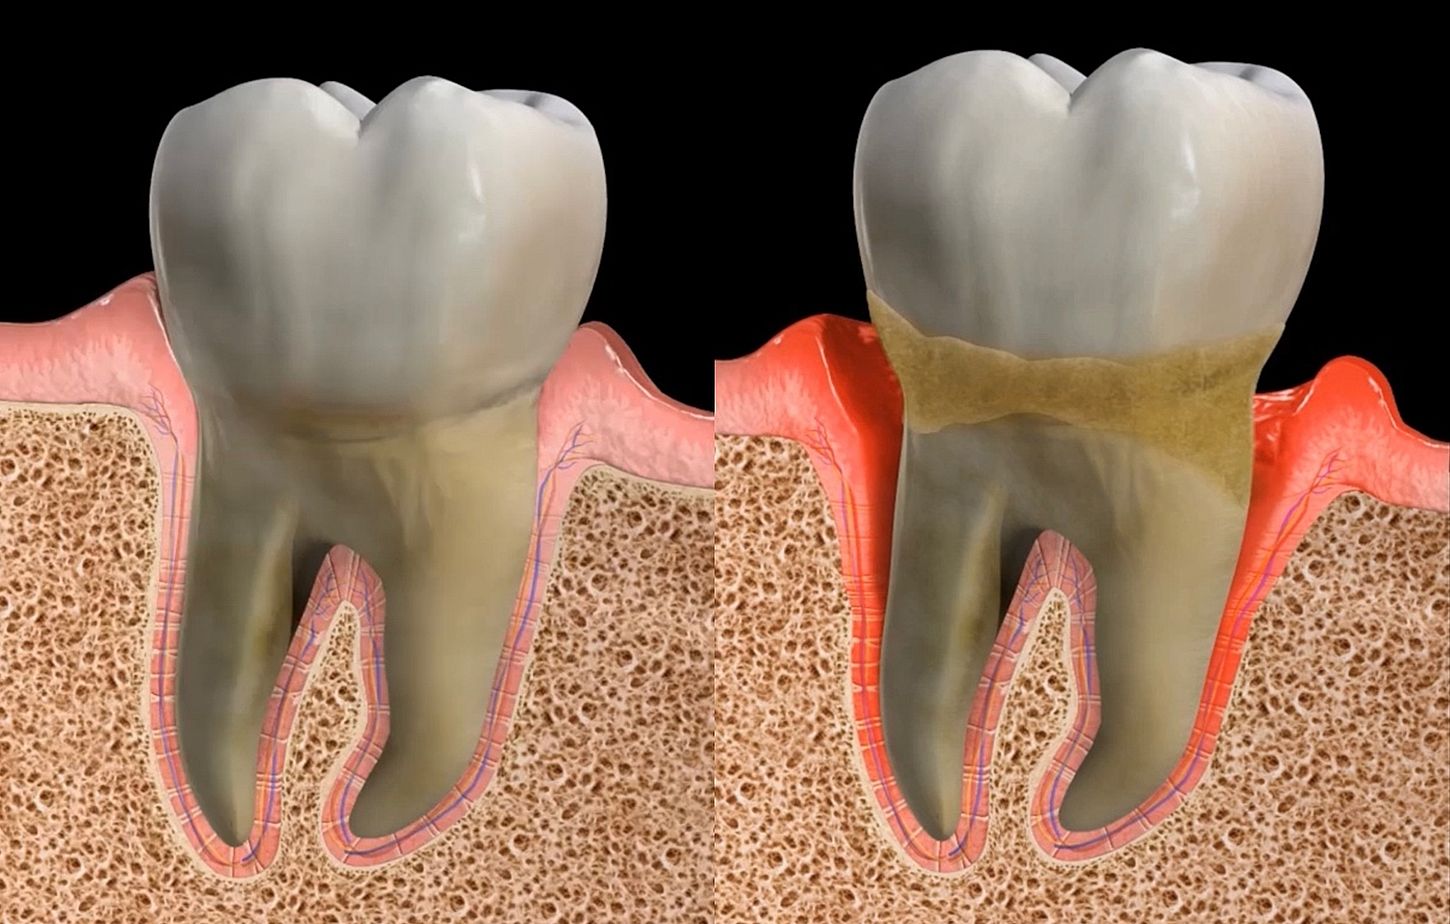

Inicialmente, debido al acúmulo de placa entre la encía y el diente, todos los pacientes desarrollan gingivitis (inflamación de la encía sin destrucción de los tejidos de soporte). Sin embargo, la mera presencia de bacterias no implica que pueda existir una progresión a periodontitis (destrucción del periodonto), puesto que se requieren otra serie de factores.

La periodontitis se trata de una enfermedad multifactorial o probabilística, en la que existe una interacción entre genes y medio ambiente. Para que exista periodontitis, deben existir unas bacterias específicas que, sumadas a una serie de factores de riesgo biológicos (enfermedades sistémicas, genética, respuesta inmune) y ambientales (higiene oral, tabaco, estrés), desencadenan una serie de cambios metabólicos que provocan la destrucción del periodonto (encía, cemento radicular, hueso alveolar y ligamento periodontal.